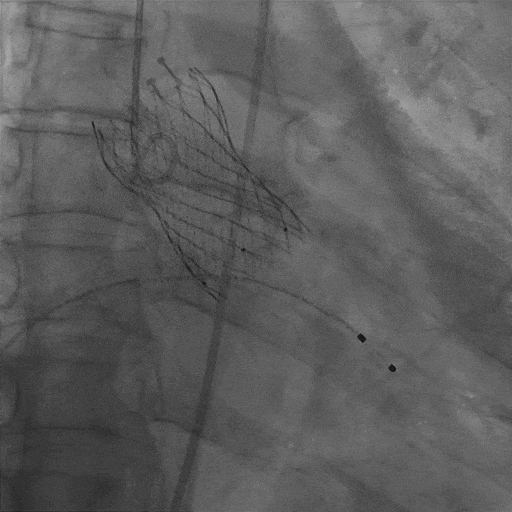

左冠保护下THV过弓及跨瓣

S3定位及植入